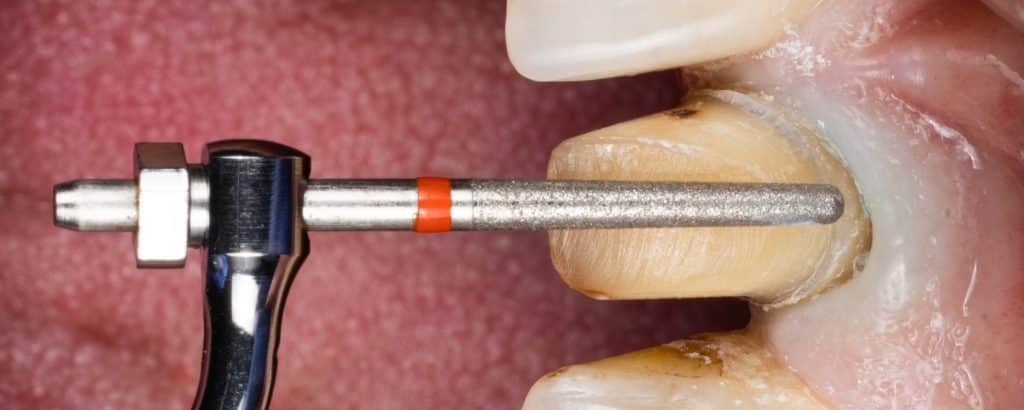

Ultrasonic preparation

Zoomed in